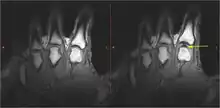

Static images of the hand in the resting phase before cracking (left). The same hand following cracking with the addition of a post-cracking distraction force (right). Note the dark, interarticular void (yellow arrow).